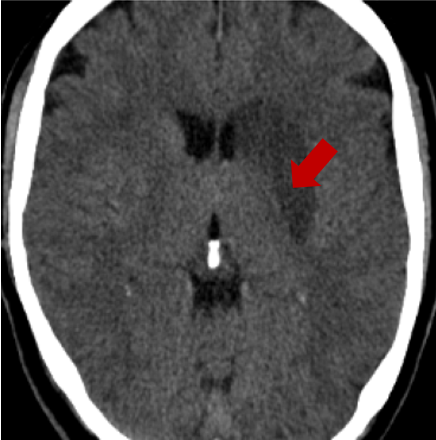

Another clinical application in which the detection of the volume of a lesion plays an important role is stroke management. In particular, it is important in the prognostic decision, in the selection process for acute treatment (Marks et al., 1999), and in anticipating complications (Mori et al., 2001). Estimates of the tissue at risk and of the ischemic core are usually derived using Computed tomographic perfusion (CTP), perfusion-weighted imaging (PWI) or MRI diffusion-weighted imaging (DWI) (Powers et al., 2019). Software packages that automatically compute these estimates from perfusion imaging were also developed to facilitate clinical decisions about stroke treatment (Mokli et al., 2019). However, Computed Tomography (CT) scans are the most commonly used tool in stroke imaging, due to being inexpensive, efficient and widely available (Mokli et al., 2019). Consequently, quantitative measurements of the signs of infarction from CT scans, while more difficult to perform than on perfusion images, would be helpful in clinical practice.

The former is a randomised-controlled trial that collected brain imaging data, primarily CT scans, from 3035 patients exhibiting stroke symptoms. The scans were conducted at two time points: immediately after the patients’ hospital admission and again between 24-48 hours later. Radiologists involved in the trial assessed the presence or absence of early ischemic signs and recorded the location of any identified lesions for positive scans. In our analysis, we considered a total of 5681 scans, of which were classified as negative (no lesion), while the remaining scans were positive. In particular, We considered 11 slices for each scan and resized each slice to . For more detailed information about the trial protocol, data collection, and the data use agreement, please refer to the following URL: IST-3 information.

As annotations of lesions are not available in IST-3, we utilise this dataset primarily for qualitative evaluations. On the other hand, for the BraTS2021 dataset, we have access to lesion annotations, enabling us to conduct quantitative analysis of the anomaly maps that we create. Both datasets were divided into training, validation and test sets with a 70-15-15 split.

4.3 Counterfactual Examples

In Figures 2 and 4 we display examples of healthy images and anomaly maps obtained with the different approaches. We can observe that f-Ano GAN is not able to generate credible counterfactuals and generally produces images of poor quality and unrealistic appearance. On the other hand, the approaches based on diffusion models are able to create more high-quality results. However, the ones obtained with CG and CFG seem to present some artifacts, which may not only impact the realism of the counterfactual examples but also the precision of the anomaly maps obtained from them. In order to better quantify the capability of these methods to accurately segment pathological areas, we compute the Dice scores of the anomaly maps they generate.